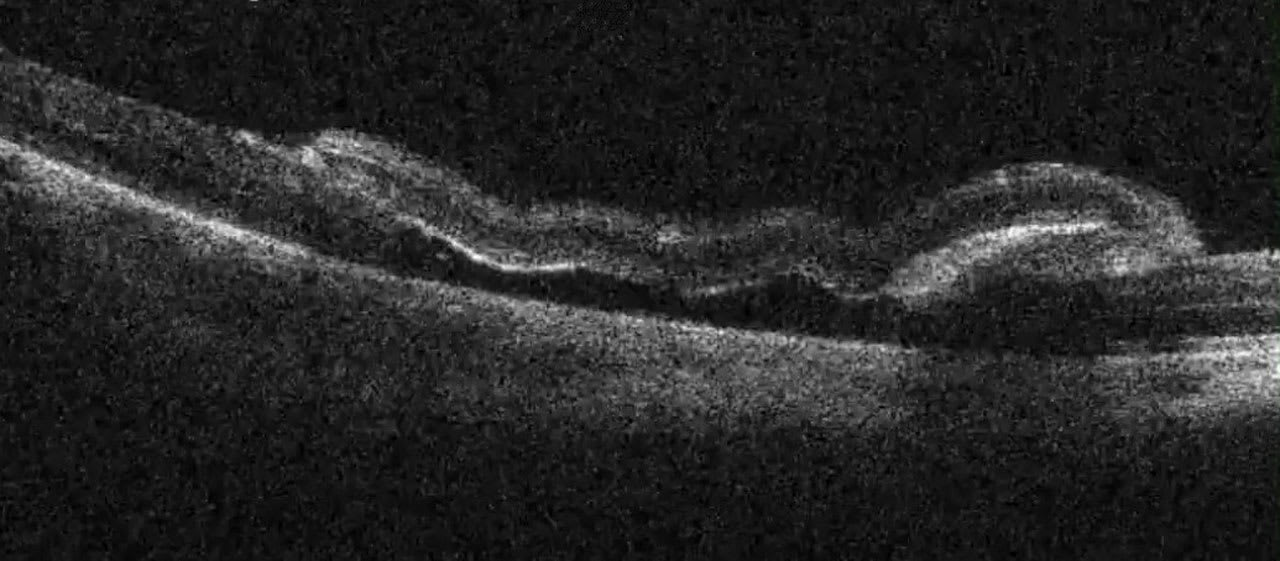

Figure 2. Still image from an iOCT scan showing the placement of an autologous retinal transplant over a large macular hole that was previously repaired but reoccurred several years postoperatively. Image courtesy Sidney A. Schechet, MD.